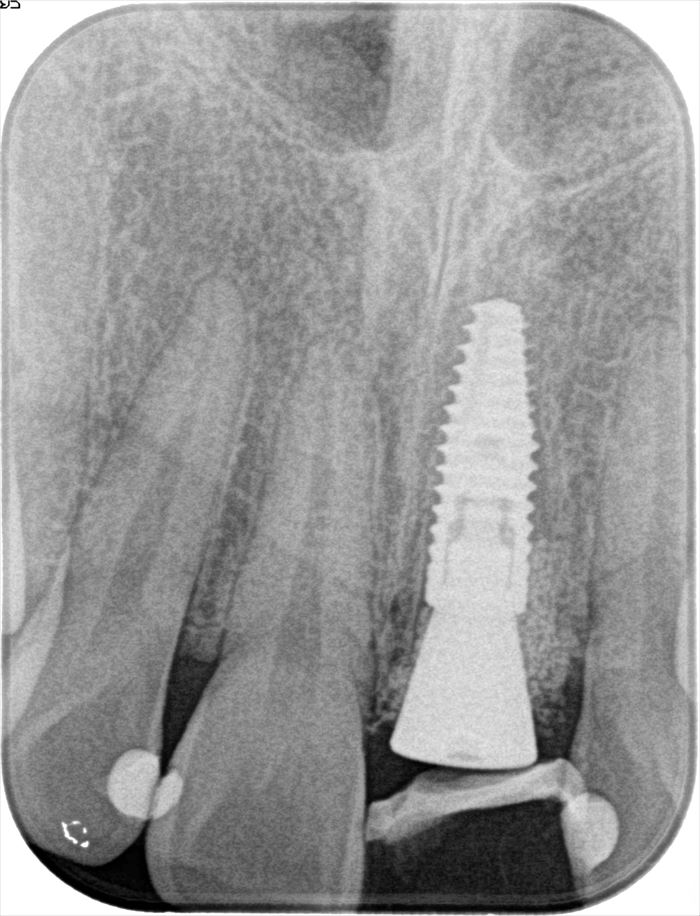

術後のデンタルレントゲン写真です。

ストローマン社製 BLT インプラント φ4.1㎜ 長さ12㎜ を用います。

インプラントの埋入を終えました。青いパーツはインプラント埋入用のパーツです。

インプラントの埋入深度は、想定する歯頚部よりも最低4㎜深い部分にインプラントネックを位置づけます。

前歯のインプラント埋入位置は口蓋側寄りにすることが審美的要件の大原則です。